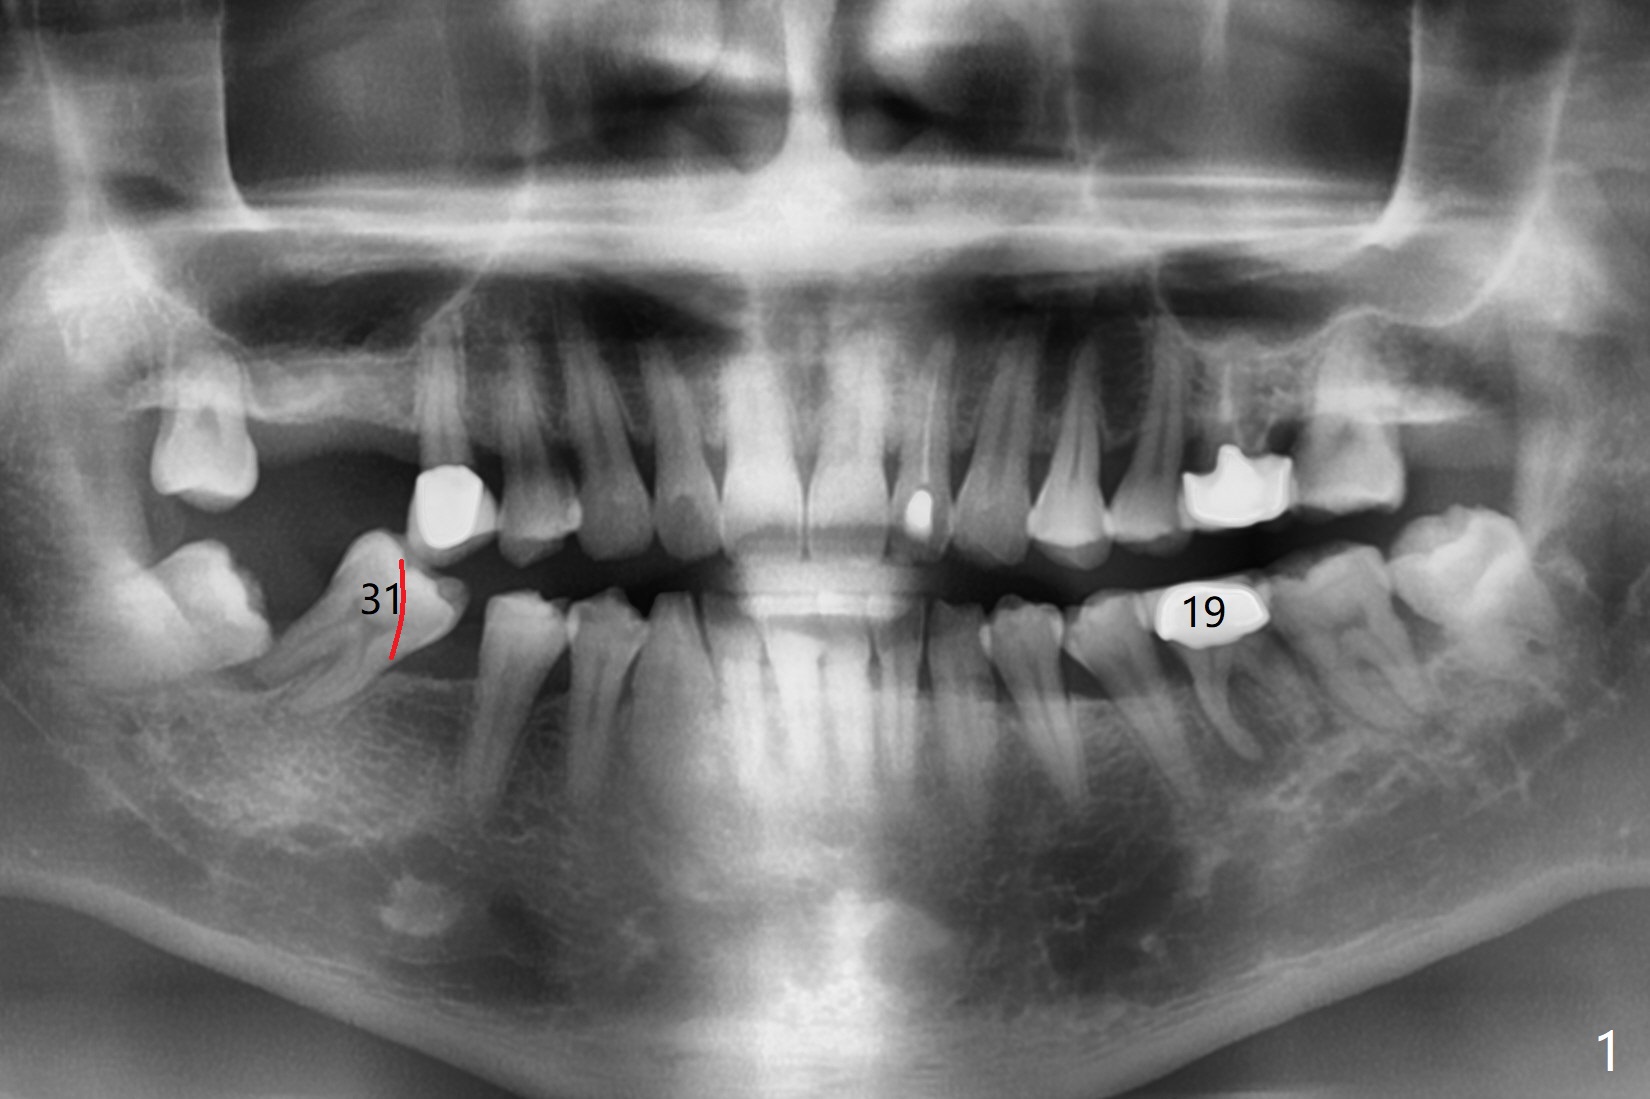

A 45-year-old man requests extraction of #19 because of endodontist's diagnosis of root fracture (Fig.1). CT shows typical apical periodontitis (Fig.2) without sign of root fracture (profilogram, data not shown), although the buccal plate of the mesial root is lost (Fig.3). Ideally 2 implants should be placed in UR and LR quadrants to prevent #19 root fracture after RCT (Fig.4). Alternative way is to place an implant at #3 (5x7.3 mm) and #30 immediately after #31 extraction. In fact a surgical guide for #30 will be fabricated resting the distal aspect of the tilted tooth #31 after sectioning the mesial portion in the lab (Fig.1 red line).